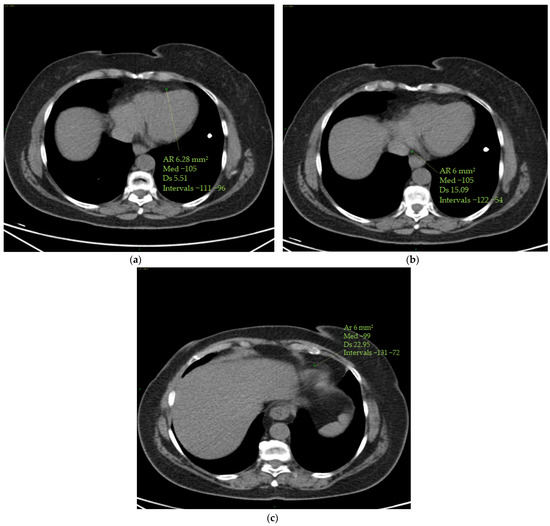

To calculate the ECV, the operator selected the optimum slice to observe the four cardiac chambers from an axial perspective.

The measurements were taken by manually inserting one ROI in the left ventricle’s ‘blood’ pool and a second ROI in the middle of the interventricular septum, avoiding papillary muscles. The same ROIs were set in the pre-contrast and post-contrast scans (portal phase). ROIs were measured in two stages (basal and portal) at time 0 and at the end of chemo-immunotherapy to provide Hounsfield units (HUs) to be used in the ECV calculation.

Standard deviations of ROIs were calculated to avoid contamination of myocardial HU measurements by motion artefacts. Altered values were not considered in this study (Figure 1).

Figure 1. ECV measurement. Myocardial and blood pool HU values were obtained on the four cardiac chambers’ projection from an axial perspective on CT scans by manually inserting one ROI (with a mean area of 6 mm2 ca) in the middle of the interventricular septum and a second ROI (with a mean area of 6 mm2 ca) in the left ventricle’s ‘blood’ pool. Papillary muscles were avoided. The ROIs were set to the same level both in the pre-contrast scans (a) and in the post-contrast scans (at portal phase) (b). ROI standard deviations were calculated to avoid contamination of myocardial HU measurements by motion artefacts. The figure shows an example of the area of the region of interest (Ar ROI), the mean (med), the standard deviation (Ds) and the range(intervals) of hounsfield units measured.